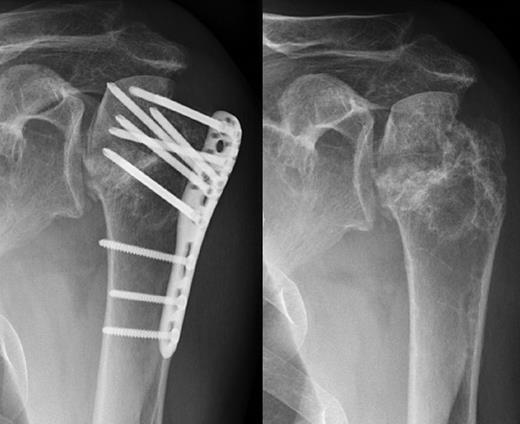

A 48-year-old patient was referred to a level I trauma center after the first incidence of an epileptic convulsion. The patient was alert and oriented with retrograde amnesia from the time of convulsion. Peripheral neurology was normal. The X-rays showed bilateral posterior shoulder dislocation with fractures of both humeral heads (Fig. 1). A CT of the head and both shoulders was performed to exclude intracerebral pathology and to achieve better demonstration of the shoulder fractures (Fig. 2). According to the AO fracture classification, he had a 11-C3.1 fracture on the left side and a 11-C3.3 fracture on the right side. The right side fracture was treated with a cementless hemiarthroplasty (OrTra®, Zimmer, Germany), while an open reduction and internal fixation (ORIF) with an angular stable plate (Philos®, Synthes, Germany) was performed on the left. Despite the high incidence for humeral head necrosis after ORIF in this fracture type, this option was chosen based on the young age of the patient. Postoperative X-rays and CT showed adequate positions of the implants (Fig. 3). The shoulders were immobilized in Gilchrist bandages followed by passive mobilization for the first 6 weeks by physiotherapy with a limitation for abduction and anteversion to 90°. There were no complications intraoperatively or in the first postoperative time. Patient was discharged after 8 days. Antiepileptic therapy was initiated with 5 mg clobazam and subsequent increasing doses over the following weeks. There were no more signs of epilepsy in the follow-up. A CT 4 months after operation showed dislocation of a fragment on the left side which was subsequently resected. At the 1-year postoperative review, the patient showed impingement of the left shoulder with abduction limited to 50° by both the plate and an osteophyte. Radiological assessment revealed signs of necrosis of the head. The plate was removed and the osteophyte resected. Eighteen months after injury, the left shoulder showed progressive avascular osetonecrosis of the head (Fig. 4) and after plate removal an inversed prosthetic replacement had to be performed (Fig. 5). At the last follow-up 3 years after injury, the patient was free of pain with a bilateral range of motion of 90° abduction and elevation.

Avascular head necrosis over the following one and a half years on the left side with ongoing necrosis after plate removal.